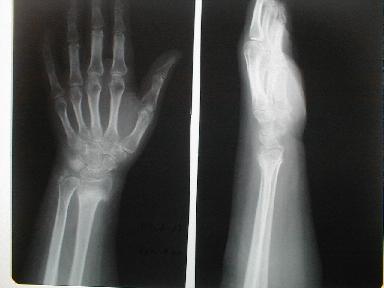

3月19日 受傷 42日目

仮骨形成は良好だが、背屈回外運動制限と運動痛は著明